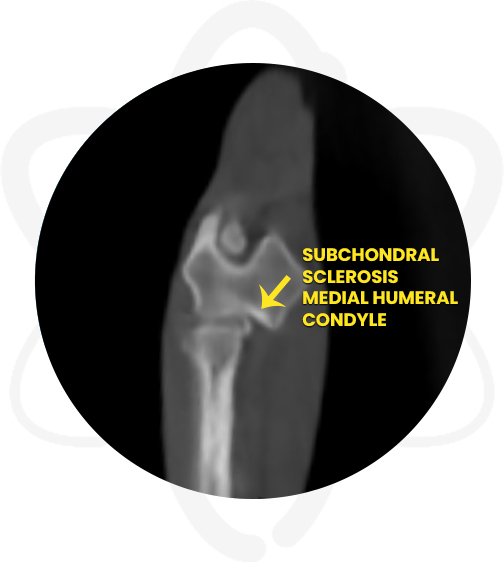

- Moderate complex joint incongruity right elbow joint and moderate subchondral bone sclerosis medial humeral condyle

Patient is a 1 yr old, MN, Pomeranian that presented to orthopedic surgeon for evaluation of a grade II lameness (of weeks duration) affecting the right thoracic limb. Physical exam and radiographs revealed that the right elbow is not congruent when in flexion and the anconeus appears less dense and blunted. A CT scan of the elbows was requested to further evaluate the joints.

- Provided the surgeon specific information regarding the suspected right elbow joint incongruency and determine the best treatment plan.